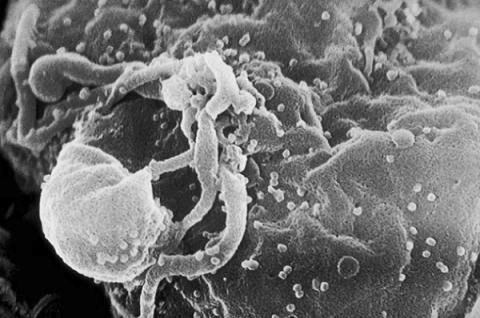

Що таке лямбліоз? Збудником хвороби є найпростіші мікроби, що паразитують в організмі людини. Джерелом часто є людина-носій, інвазірованний лямбліями.